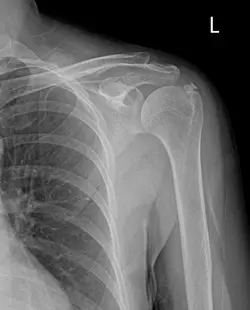

석회성 건염은 어느 순간 이유도 없이 통증이 와서 어깨를 잘 움직이지 못하는 게 특징이며 비교적 진단이 쉬운 질환이다. X-ray 검사로 석회가 낀 것을 확인할 수 있는데, 방사선 비투과성 병변 부위가 하얗게 1~2mm부터 3cm까지 다양한 크기로 발견된다.